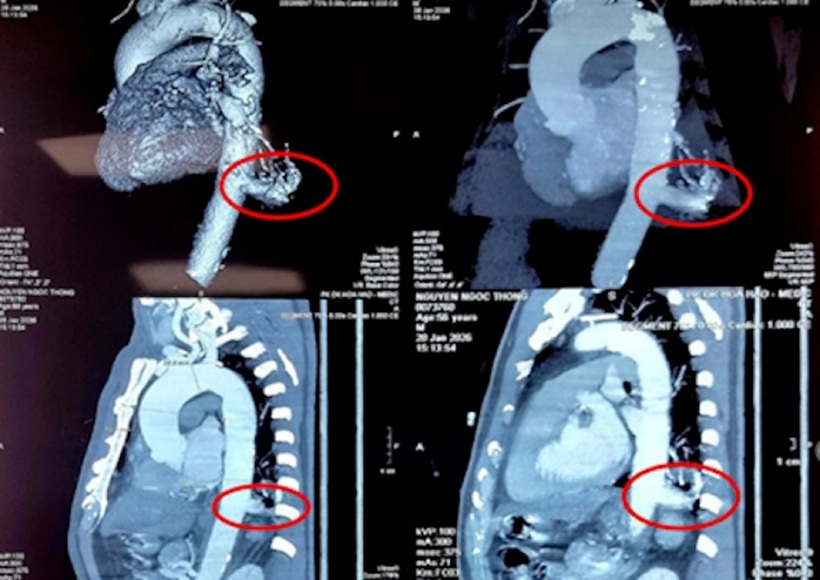

Ảnh chụp phim phần phổi dư thừa của bệnh nhân. Ảnh: Vnexpress.

Theo đó, bệnh nhân N.N.T (56 tuổi, Tây Ninh) tình cờ phát hiện tổn thương thùy dưới phổi trái khi đi khám tổng quát. Kết quả chẩn đoán hình ảnh tại Bệnh viện Bình Dân ghi nhận khối tổn thương có kích thước 23x26mm - đủ để xác định ông T. mắc phổi biệt lập nội thùy.

Động mạch nuôi khối này xuất phát trực tiếp từ động mạch chủ xuống, đường kính lên tới 17mm, kích thước rất lớn và rủi ro nếu bệnh nhân không được điều trị.